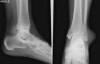

X-ray : 발목 점액낭염(Ankle bursitis)

Lateral malleolus의 subcutaneous bursitis입니다.

자주 정좌를 하는 사람에게는 족관절 전외측, 외과전방에 색소침착이나 굳은살이 생깁니다.